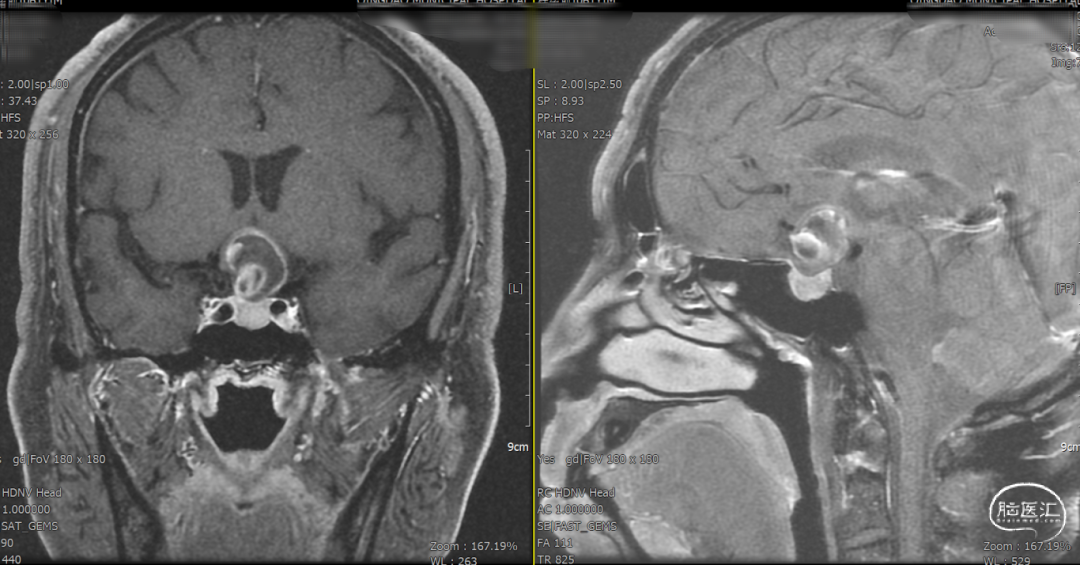

辅助检查示:2025-01-08 鞍区及垂体MR平扫:鞍内及鞍上肿瘤,垂体瘤并卒中?建议鞍区及垂体MR增强扫描。

2025-1-19 DSA造影3D重建及方案讨论:

DSA造影3D重建测量

拟行脑动脉瘤密网支架置入术。